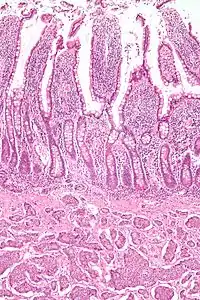

| Micrograph of a neuroendocrine tumor. H&E stain. | |

NETs are often small, yellow or tan masses, often located in the submucosa or more deeply intramurally, and they can be very firm due to an accompanying intense desmoplastic reaction. The overlying mucosa may be either intact or ulcerated. Some GEP-NETs invade deeply to involve the mesentery.[72] Histologically, NETs are an example of "small blue cell tumors," showing uniform cells which have a round to oval stippled nucleus and scant, pink granular cytoplasm. The cells may align variously in islands, glands or sheets. High power examination shows bland cytopathology. Electron microscopy can identify secretory granules. There is usually minimal pleomorphism but less commonly there can be anaplasia, mitotic activity, and necrosis.